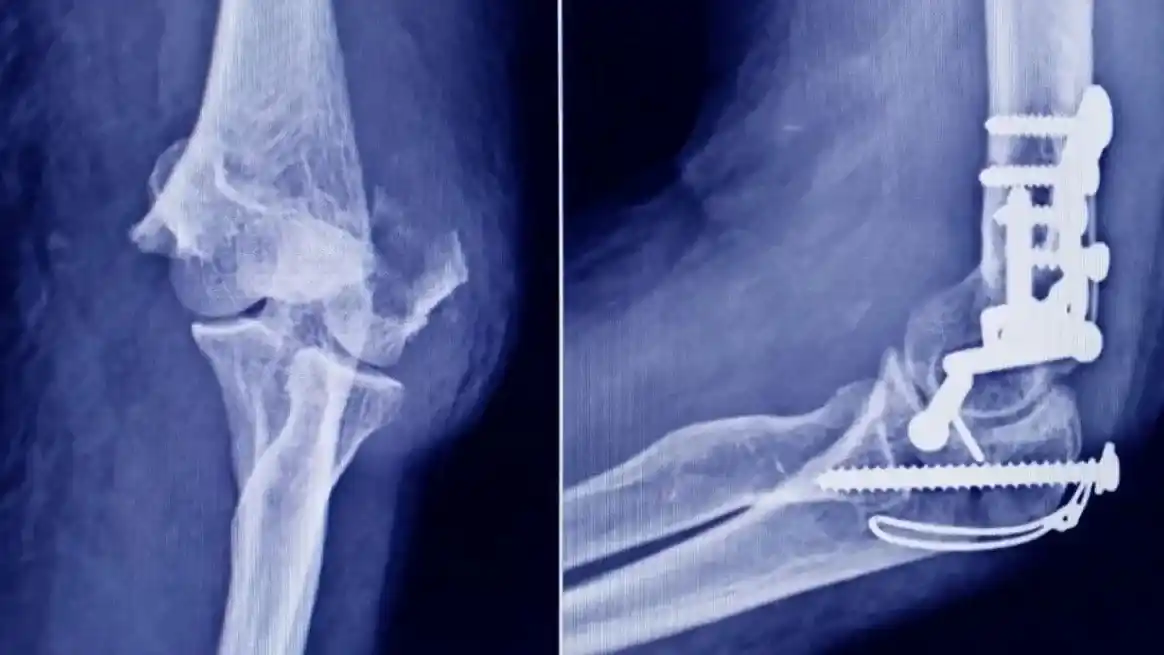

El caso más relevante fue el de un tornillo de interferencia para ligamento cruzado, rotulado como perteneciente a la marca Stryker. Tras un análisis detallado, se determinó que se trataba de una falsificación.

Las diferencias con el producto original fueron contundentes. Mientras el implante legítimo presenta un color gris opaco, el detectado era incoloro y translúcido, lo que sugiere una composición distinta. Además, el empaque no coincidía con los estándares del fabricante: estaba contenido en una bolsa tipo pouch de una marca que no es utilizada por la empresa original.

Otro punto clave fue el método de esterilización. El producto auténtico se esteriliza mediante radiación gamma, mientras que el hallado indicaba haber sido preparado para esterilización por vapor o formaldehído, un procedimiento incompatible con ese tipo de dispositivo.

A esto se sumó la ausencia de datos esenciales, como la fecha de vencimiento, y la detección de que el lote correspondía a una referencia que dejó de fabricarse en 2024 y cuya vigencia original habría expirado entre 2015 y 2016.

En el caso del tornillo falsificado, la incertidumbre sobre su composición y resistencia mecánica abre la posibilidad de fallas estructurales una vez implantado. En cirugías como las de ligamento cruzado, este tipo de dispositivos cumple una función clave en la estabilidad de la articulación.